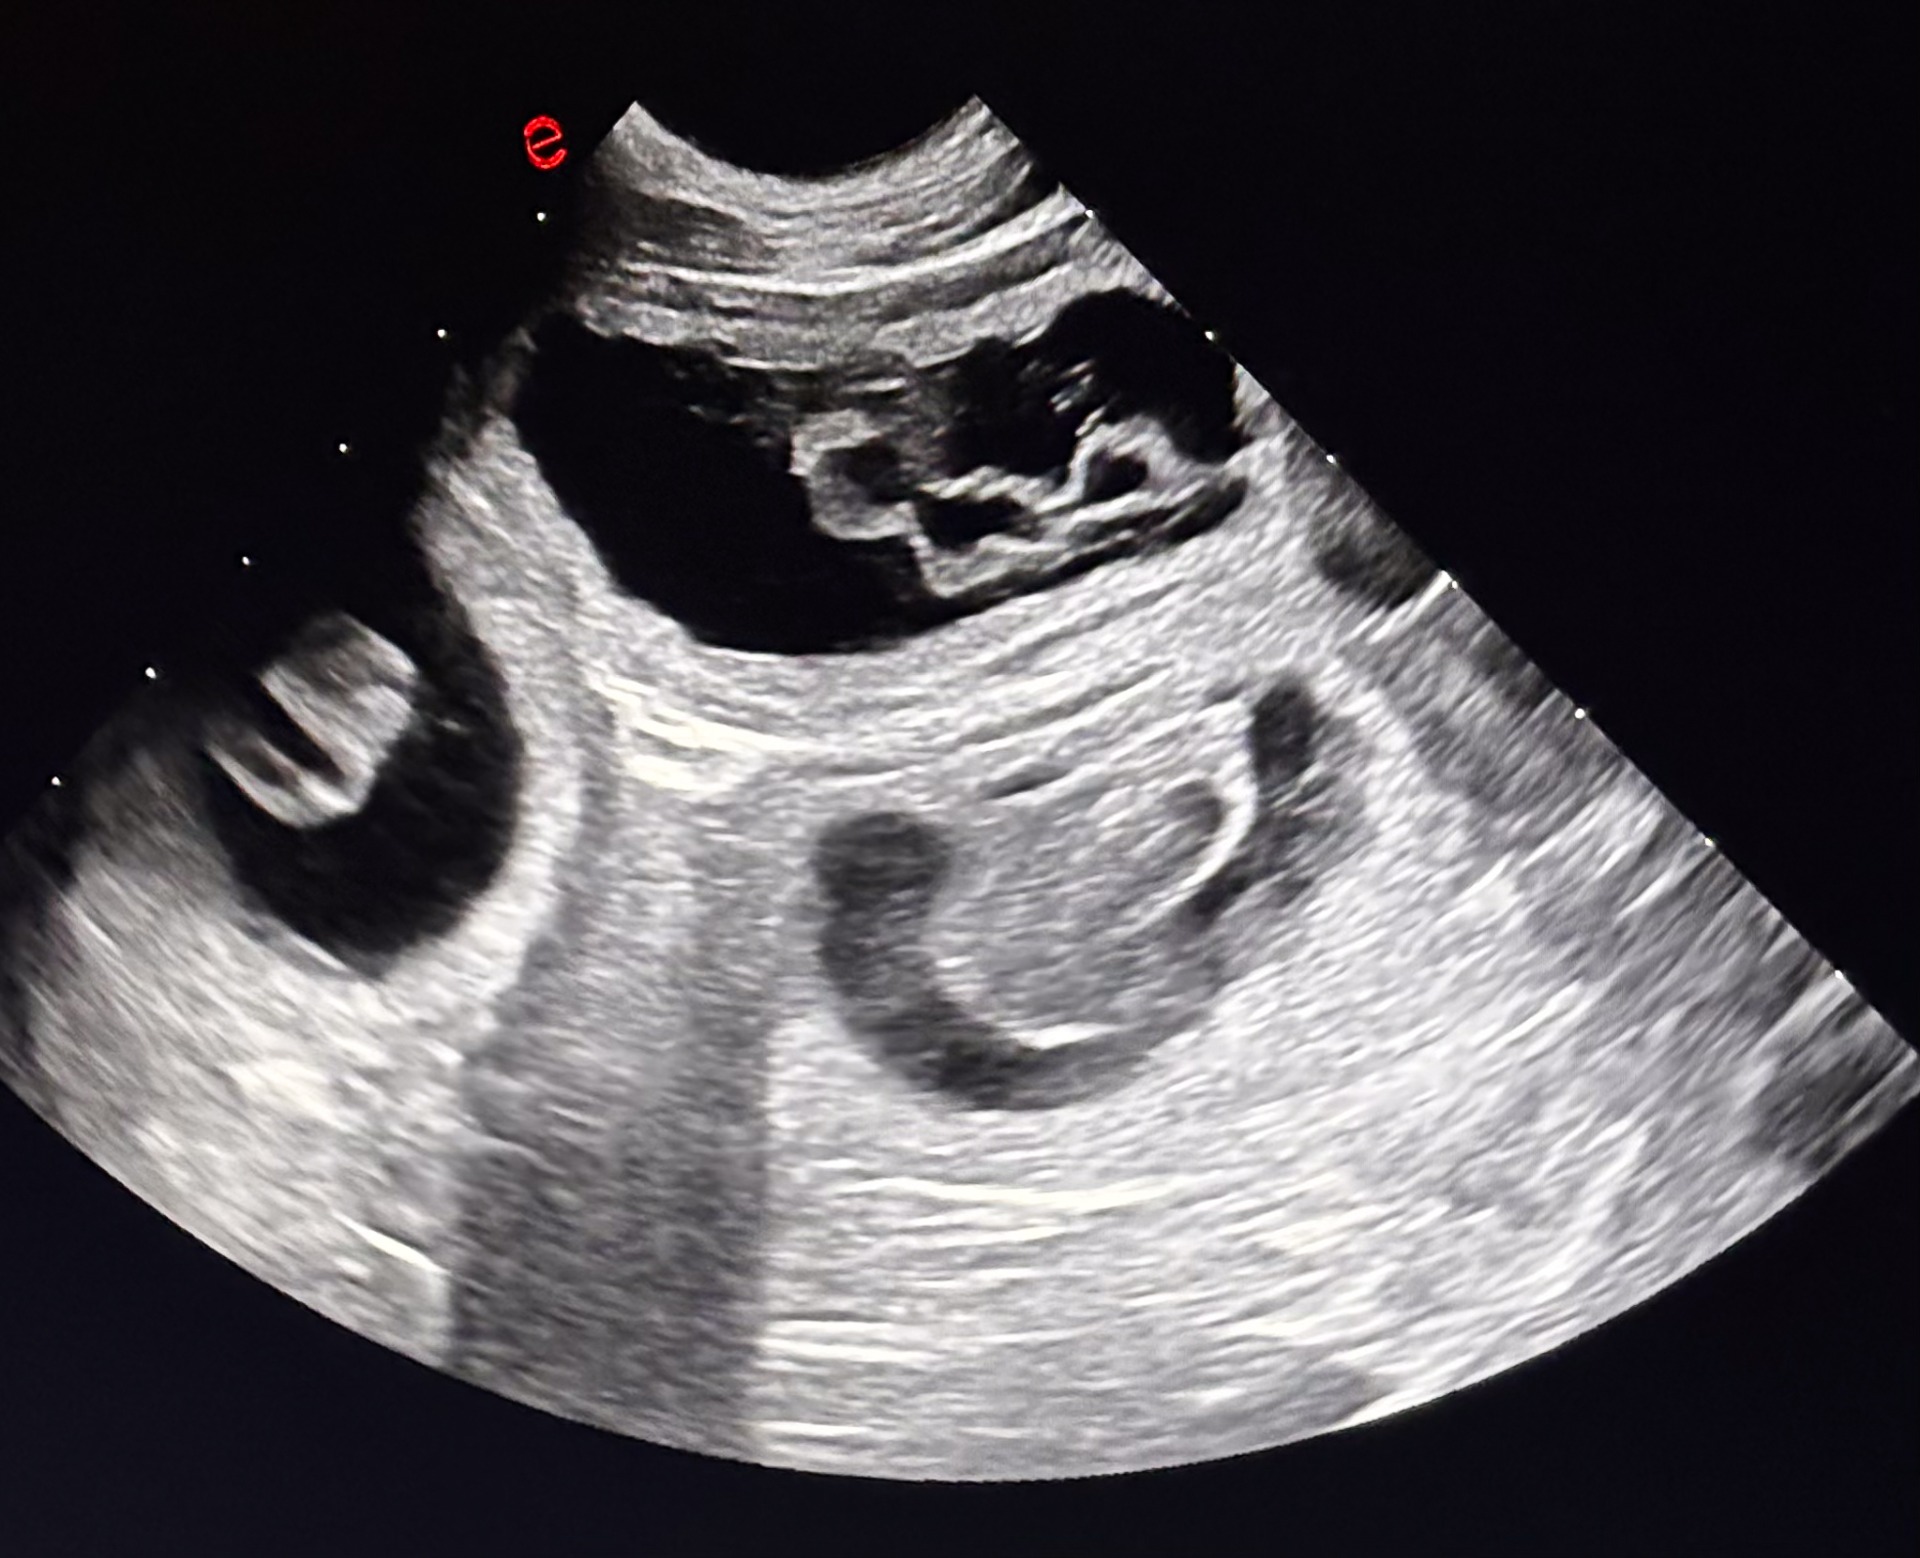

Május közepén érkeznek Aleu és Scotty kiskutyái!

Ennek a párosításnak nagyon hosszú története van és NAGYON régen megszületett a fejünkben. Ennek ellenére akkor, amikor a H alom megszületett, Bria maradt velünk és a GG mentes Aleu különleges, "hátha lesz belőle valami" megállapodással költözött el. Már akkor tudtam, hogy szeretném ezt a párosítást, utána pedig amikor végül családi okok miatt Aleuci visszaköltözött hozzánk, egyértelműen közelebb kerülhettünk ehhez a párosításhoz. De ekkor még évek munkája várt ránk, hogy a párosításnak akár csak a gondolata is megfordulhasson a fejünkben. Sokat és sokan dolgoztunk érte, hogy létrejöhessen végül, nagyon sokat is vártunk vele, de annál nagyobb boldogsággal várjuk a kiskutyákat belőle, akik egy általunk tisztelt kutyára való távoli vonaltenyésztés eredményei lesznek így.

Az alom másik hatalmas különlegessége számunkra, hogy nagy büszkeségünk Scotty első fedezéséből várjuk a kicsiket, aki az első kutya kennelünkben, aki InterChampion címet szerzett a csodálatos kiállítási eredményeivel (kicsit lejjebb), és nagyon vártuk, hogy végre továbbvihessük az ő genetikai és eszmei értékeit, amit számunkra és a Gazdija, Klaudia számára jelent. Több okból rendkívül különleges számunkra ez az alom.

FONTOS KIEGÉSZÍTÉS, hogy Aleunak mindössze ezt az egy almot vállaljuk, hiszen csak emiatt a párosítás miatt maradt 3,5 éves koráig ivarosan, az alom felnevelése utána ivaratalanítjuk őt, így ez egy igazán egyedi és ettől még értékesebb párosítás lesz a számunkra. Nem titkolt szándékunk társtulajdonban kölyköt elhelyezni a párosításból, így ehhez komoly hozzáállású érdeklődést még fogadunk kiállításra nyitott és elhivatott érdeklődőtől, de pont az alom megismételhetetlensége és különlegessége miatt valóban elkötelezett Gazdi érdeklődését várjuk, aki átérzi majd a kiválasztott kiskutya eszmei értékét.